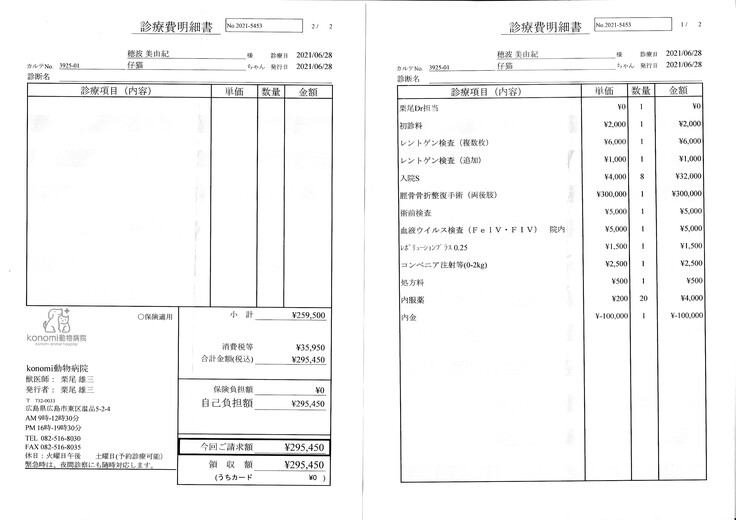

明細書

①入院費用

②退院後の飼育と治療